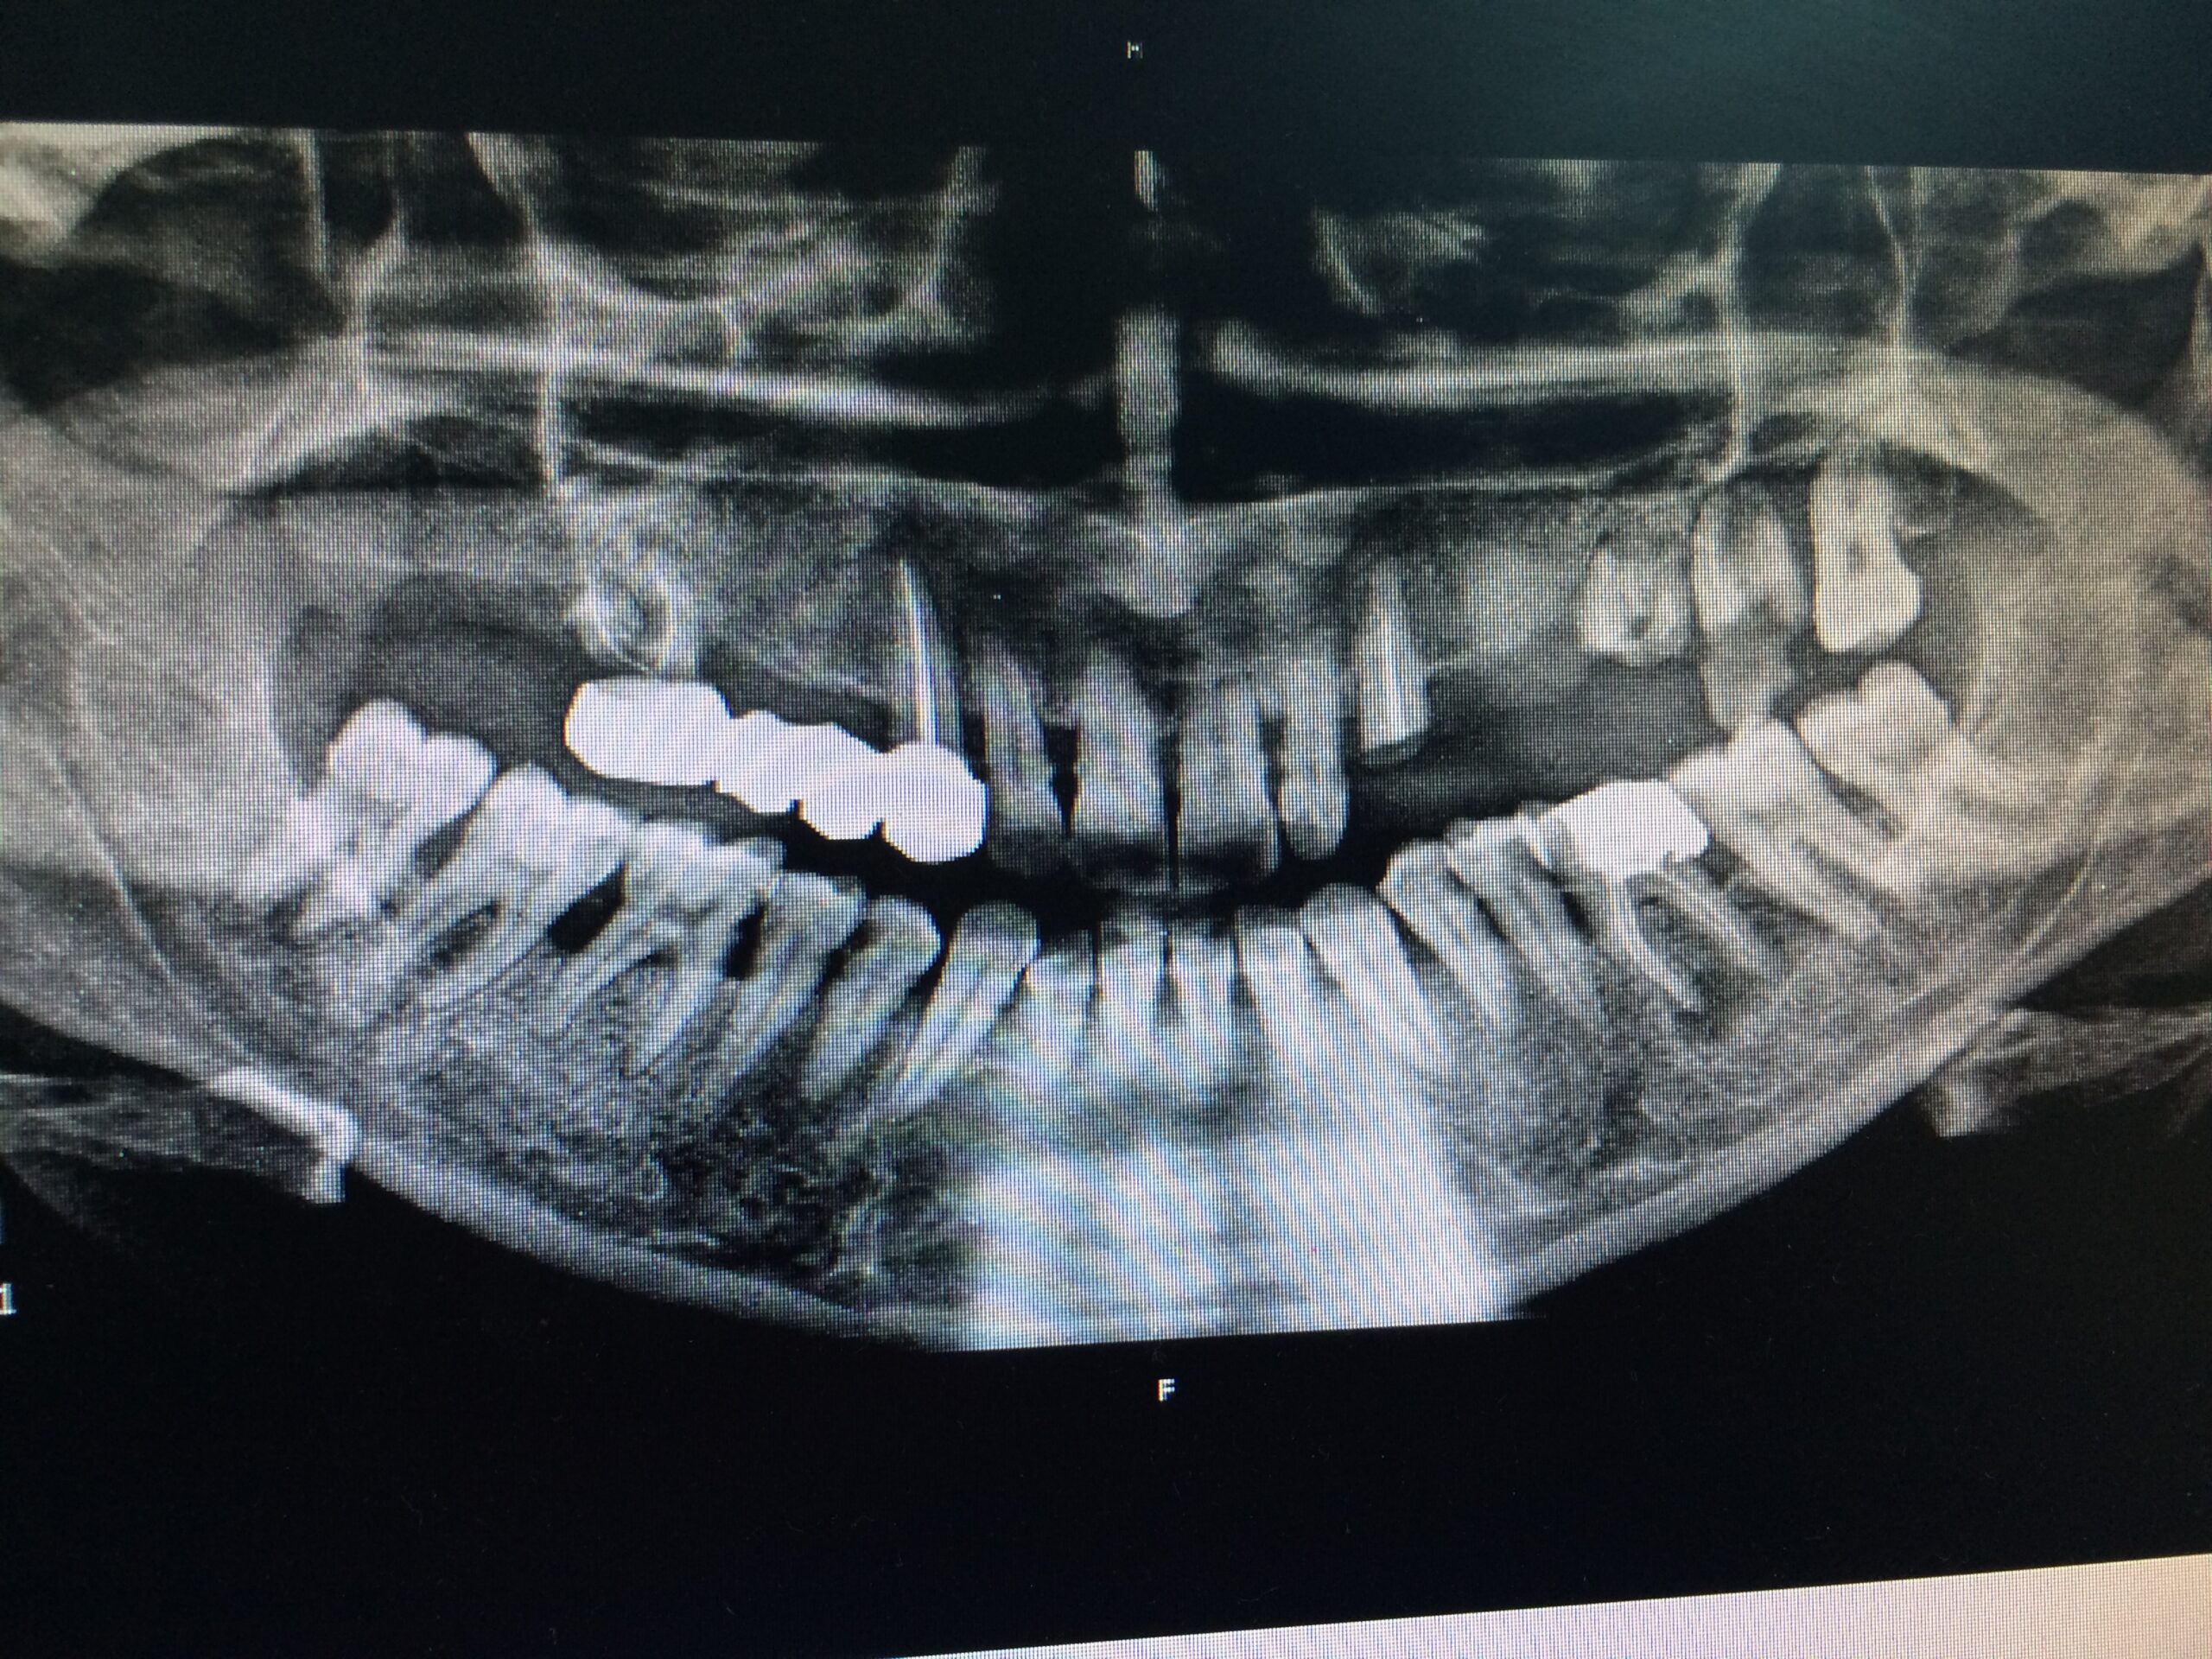

La pose d’un implant dentaire s’effectue en plusieurs étapes étalées sur quatre à neuf mois, et en règle générale, de la façon suivante :

→ Avant l’intervention

Après une étude approfondie de vos antécédents dentaires et médicaux, le dentiste détermine si les implants dentaires sont indiqués dans votre cas. Il examine ce qui doit être fait, se prépare et vous explique en plan de traitement à venir.

→ Pose du ou des implants

Durant cette étape, le praticien pose les implants dentaires pour remplacer les racines manquantes. À l’issue de cette intervention, vous sentirez des implants couverts par la gencive, et qu’ils sont mis en “nourrice” : cela permet à l’os de cicatriser autour des implants.